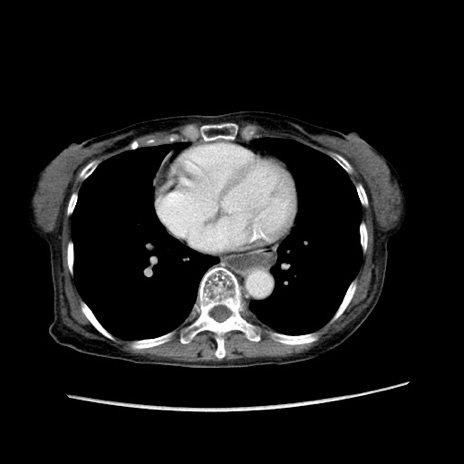

冠状断像

【症例】80歳代女性

【主訴】胸のつかえ感

【現病歴】約9時間前に食後から胸のつかえた感じあり、嘔吐あり、来院。

【既往歴】胃癌(全摘)、胆摘、虫垂炎

【身体所見】心窩部に圧痛あり、反跳痛なし。

【データ】WBC 5700、CRP 0.05